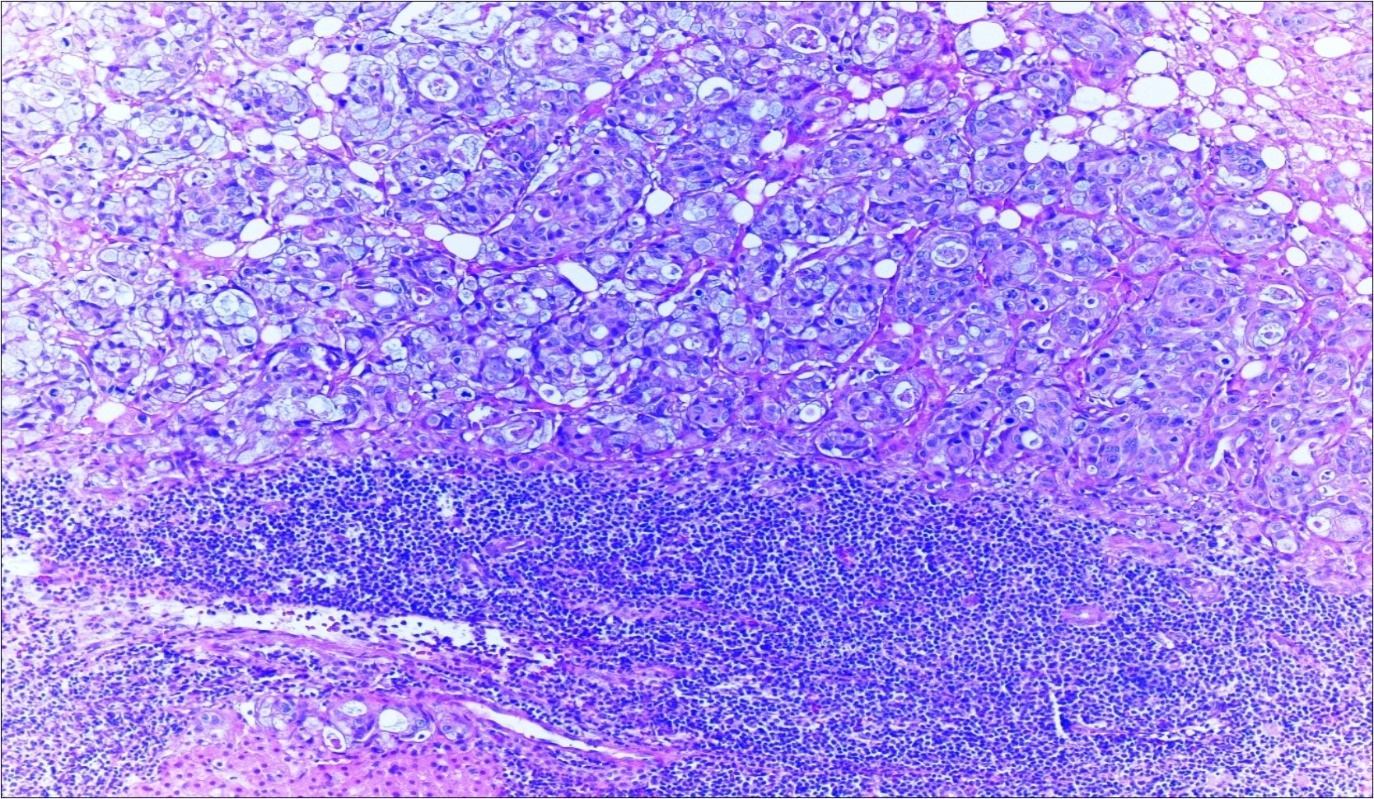

A 63-year-old woman presented to the Department of General Surgery as an outpatient with abdominal pain. Physical examination showed the signs of acute appendicitis and appendectomy was performed. During microscopic examination, a small focus of atypical monotonous lymphoid cell population was seen and the material was sampled totally. The pathological examination revealed MALT lymphoma (Figure 1), with diffuse positivity of cluster of differentiation (CD) 20 (Figure 2), CD 79a and B-cell lymphoma (Bcl- 2) (Figure 3) with just a few CD3 positive lymphoid cells. However, no evidence of adenocarcinoma was found in the appendectomy specimen. After the diagnosis of lymphoma, a complete colonoscopy was planned and this revealed a solid tumoral mass in the caecum measuring 5x4x4 cm. Computed tomography of the abdomen and pelvis revealed mesenteric lymphadenopathy associated with a mass in the caecum with multiple nodules in liver consistent with metastasis (Figure 4). Frozen sections were not obtained since the treatment method would not be affected. The patient underwent anterior resection with regional lymphadenectomy, with the pathological assessment of the resected specimen revealing a collision tumor consisting of a poorly differentiated adenocarcinoma extending through the muscularis propria with MALT lymphoma (Figure 5). Microscopic evaluation of the 11 regional lymph nodes in the mesentery of the resected colon and liver biopsy showed diffuse infiltration of MALT lymphoma with metastasis of adenocarcinoma (Figure 6). According to immunohistochemistry, atypical lymphocytes were positive for CD 20, Bcl-2, and negative for CD3, CD5, CD10, CD23, Bcl-6, terminal deoxynucleotidyl transferase, and cyclin D1. The proliferation fraction (MIB-1 immunostaining) was approximately 20%. The morphological and immunohistochemical findings were used to confirm the diagnosis of synchronous presentation of MALT lymphoma and colon adenocarcinoma within the caecum, mesenteric lymph nodes and liver metastases.

Figure 5.Adenocarcinoma with MALT lymphoma infiltration of colon (h&e;200)

Adenocarcinoma with MALT lymphoma infiltration of colon (h&e;200)